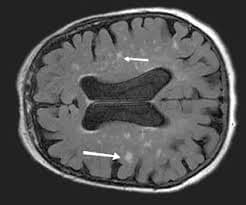

Ihneď po prijatí prebieha štandardizovaný diagnostický protokol: CT alebo MRI mozgu, laboratórne vyšetrenia, EKG a monitorovanie vitálnych funkcií v reálnom čase. Pri ischemickej príhode sa v časovom okne do 4,5 hodiny podáva intravenózna trombolýza; pri veľkých uzáveroch proximálnych tepien je indikovaná mechanická trombektómia, dostupná v regionálnych intervenčných centrách.